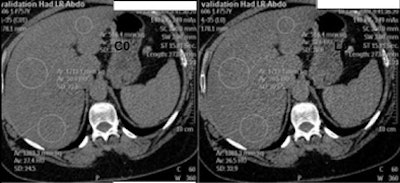

| Measuring fatty-liver attenuation in regions of interest. All images and data courtesy of Dr. Jacob Sosna. |

The clinical arm of the study was a retrospective analysis of different fat-containing pathologies, using data from pathologies containing both macroscopic and microscopic fat. Regions of interest were drawn on the CT images for both low- and high-energy scans, and measurements were compared.

The group analyzed 33 patients (mean age, 56; range, 26-85) at 3-mm slice thickness, 1.5-mm reconstruction interval, 140 kVp, and 150 mAs.

- Attenuation of fatty liver (n = 10) averaged 18 HU versus 25 HU at high energy.